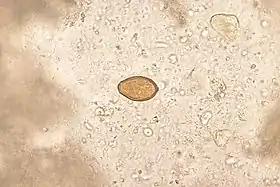

Heterophyes heterophyes

Heterophyes heterophyes é uma espécie de trematódeo da família Heterophyidae. É um parasita intestinal de humanos causando a heterofíase.[1]